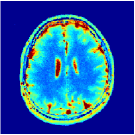

Two sets of experiments were conducted here: first, we used the 2D and 3D acquisition sequences for scanning a healthy volunteer’s brain (real-world acquisitions). Figures 6 and 7 display the parametric maps reconstructed from 2D spiral and radial readouts. We computed the T1, T2 and proton density (PD) maps using baseline reconstruction algorithms ZF, VS, LR, FLOR, AIR-MRF and our proposed LRTV. While baselines use DM either for quantitative inference or also during reconstruction (i.e. AIR-MRF), we further compare the DM-free LRTV’s performance when cascaded to DM, KM and MRFResnet for quantitative inference. For the 3D spiral acquisitions we compared LRTV and its closest competitor VS in Figure 8. Outcomes from other tested algorithm are displayed in the supplementary materials (Figure S5). Since FLOR does not use dimensionality-reduction, our system ran out of memory during 3D reconstruction; hence results are not reported in this case.

The LRTV-DM and LRTV-MRFResnet perform on par, and both outperform all tested baselines for reconstructing T1, T2 and PD maps in all acquisition schemes. This can be observed both visually in Figures 6, 7, 8, S2 and S3, and quantitatively in Table IV across all tested metrics. Other baselines were unable to successfully remove the under-sampling artefacts in TSMIs, and these errors propagated to the parameter inference phase and resulted in inaccurate maps. Temporal-only priors incorporated within LR are shown insufficient to regularise the inverse problem and LR sometimes (e.g. 2D spiral acquisitions) can admit solutions with even stronger artefacts than the model-free ZF baseline. This issue was previously studied for other non-Cartesian MRF readouts that similar to our spiral/radial trajectories, miss to sample the corners of the k-space in all timeframes (see section 2.2.2 and figure 2 in [19]). In the absence of reference for the k-space corners information, the LR iterations despite minimising the objective can converge to solutions with high-frequency artefacts, as visible in the computed maps. This highlights the need for adding an appropriate spatial-domain regularisation. FLOR reduces the LR’s artefacts but this improvement is limited because the suggested nuclear norm penalty does not incorporate an explicit spatial regularisation. Further for reducing artefacts, FLOR can introduce an undesirable bias in the computed T1/T2 maps e.g. see error maps in Figures S2 and S3. The non model-based VS baseline incorporates spatial regularisation and results in spatially smoother maps than ZF and LR, but it is unable to output artefact-free images. Further and consistent with our in-vitro experiment, we observe that VS overestimates the T2 values (e.g. in White and Grey matter regions) in tested 2D acquisitions i.e. the spatial regularisation trades off agains the quantification accuracy. The model-based AIR-MRF adds spatial regularisation through 2D/3D low-pass Gaussian filters however this trades off the sharpness of the computed maps and can increase the errors at the tissue boundaries (we searched Gaussian spreads that keep the blurs and high-frequency artefacts minimal). For our acquisition readouts, Gaussian filters performed better than disk filters of [19] for avoiding strong Gibbs artefacts. On the other hand, the spatiotemporally regularised LRTV greatly improves the TSMI reconstructions i.e. 4 dB enhancement compared to the closest competitor baseline (Table IV). This enables computing accurate and aliased-free multi-parametric inference using DM or the DM-free learning-based alternative MRFResnet as visible in Figures 6, 7, 8, S2 and S3. MRResnet and DM score competitive quantitative inference results i.e. T1 and T2 MAPE less than 5% and 9%, respectively (Table IV). KM also outputs comparably accurate T1 maps, however this shallow learning model despite having a model size larger than MRFResnet, is unable to learn accurate T2/PD quantification and it results in poor estimated maps, consistent with our observations in section VI-C.